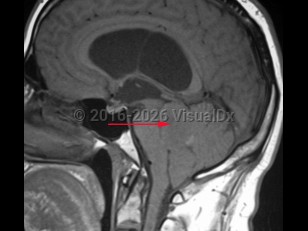

EpendymomaEpendymoma

Spinal epidural abscess

Paraspinal abscessParaspinal abscess